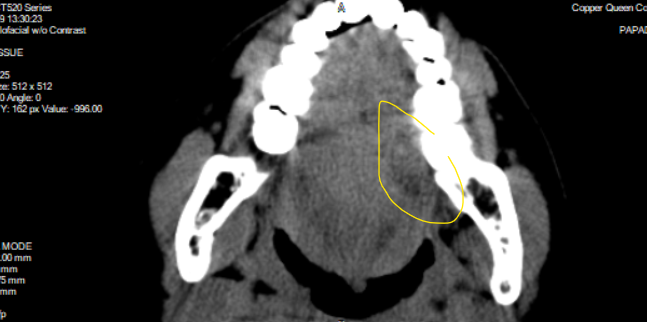

Trigeminal V3 (2?) asymmetry